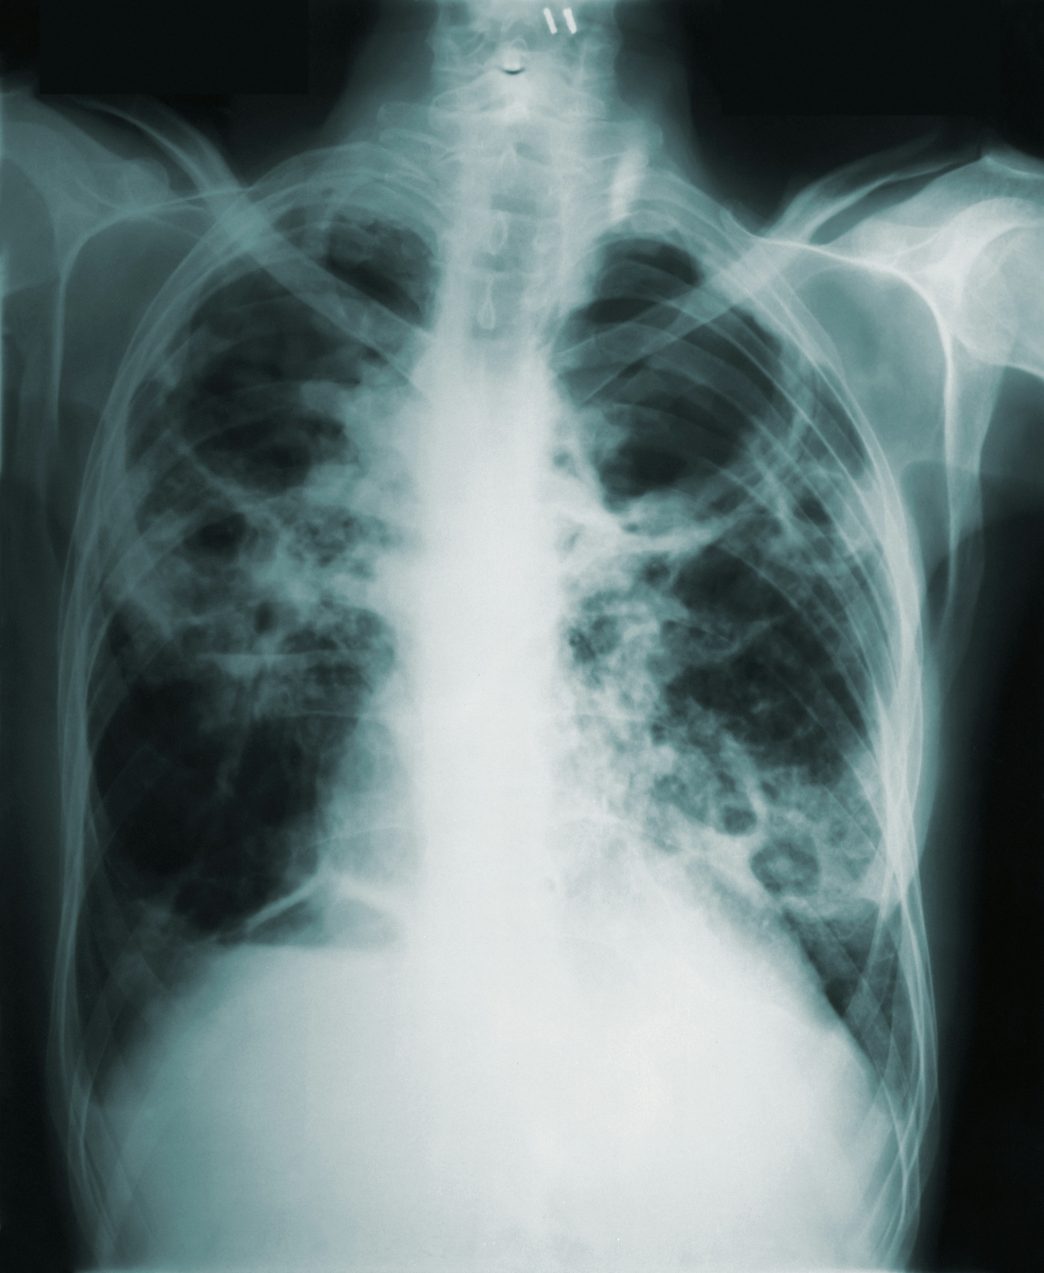

TB testing will be offered for individuals who may have been exposed. If the test is positive, the individual will be sent for a chest X-ray and then follow up with Public Health. If the chest X-ray shows no disease in the lungs, treatment for latent TB infection is recommended to prevent progression to active TB illness.